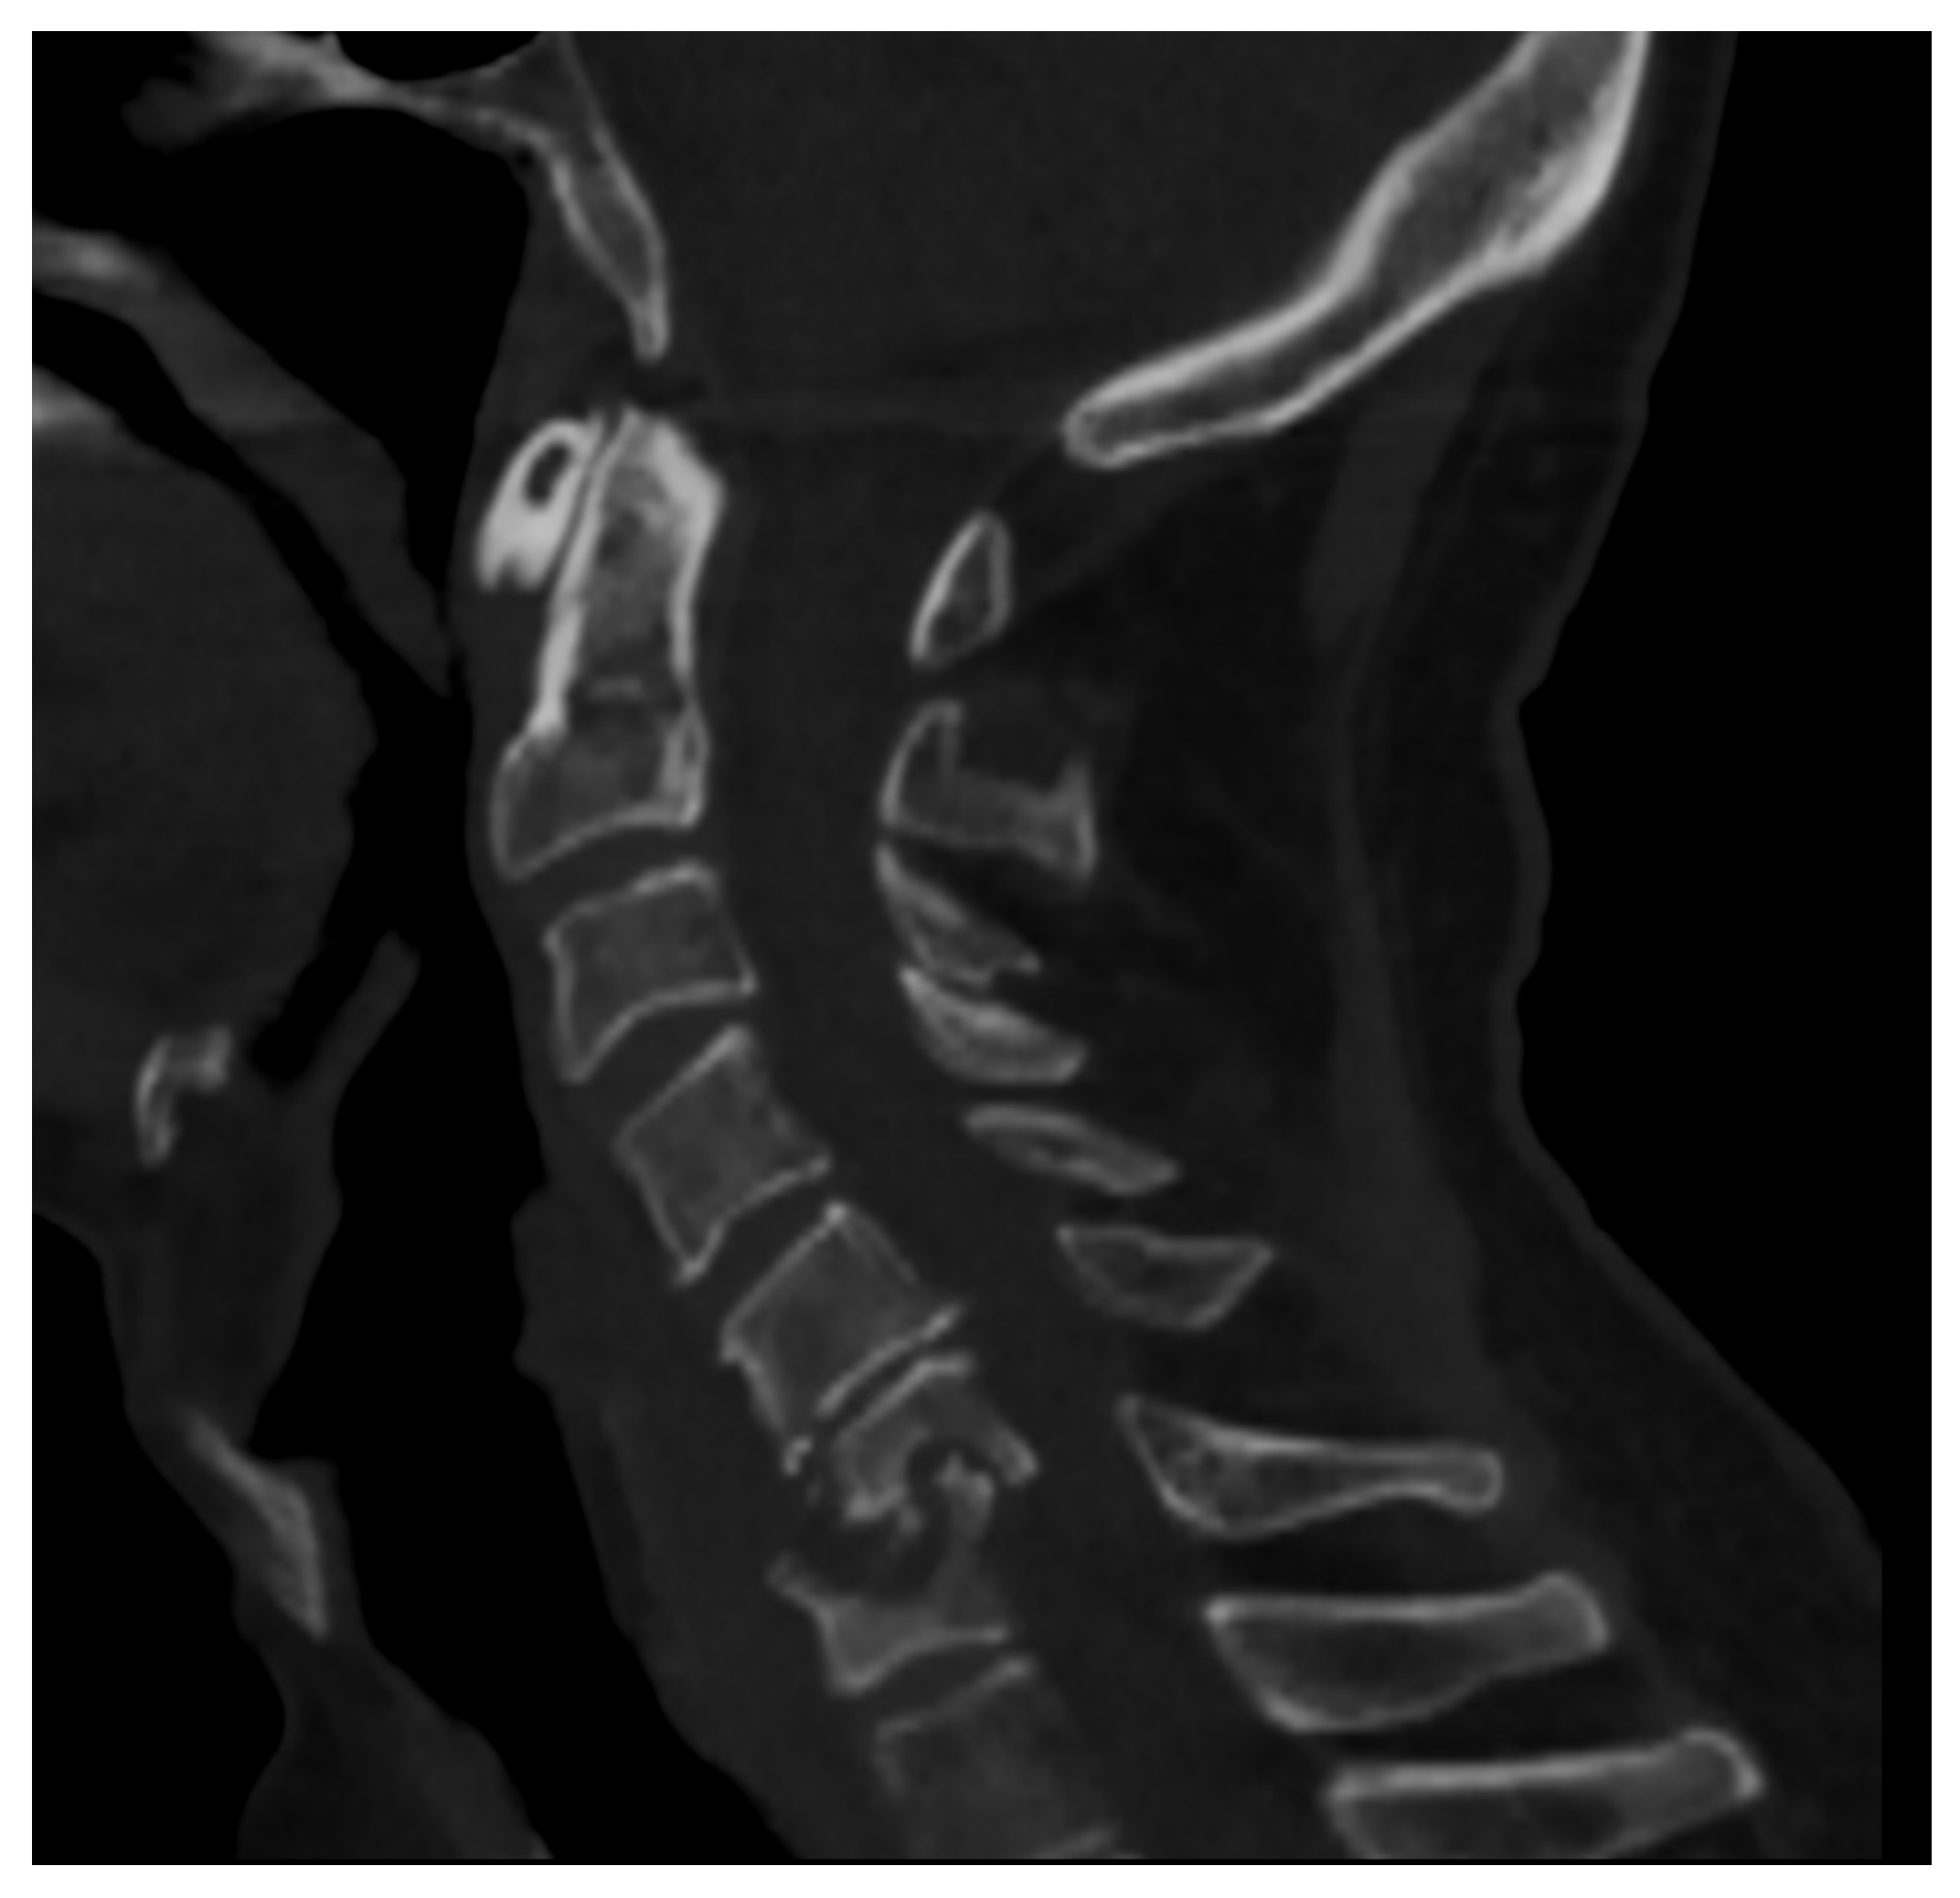

The lumbosacral region is involved in 52–58% of cases, the thoracic spine in 26–35% of cases, and the cervical spine in the remaining 10–22% of cases (Figure 1) [12].

Figure 1. CT of the cervical spine (sagittal reconstruction) of a middle-aged man (HIV+) affected by spondylodiscitis in the C6–C7 tract of the cervical spine complicated by myelopathy.